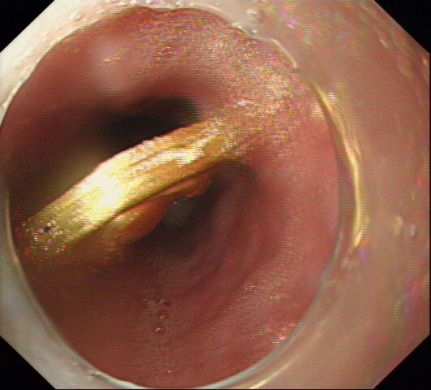

7月11日中午我院住院部消化科接到急诊科电话,一名青年男子突发胸骨后疼痛伴胸闷气急需急会诊,许丰主任赶赴急诊科,追问病史,患者因与家属“怄气”吞服一枚金制挂件,X线片提示金属异物嵌顿于食管,随时有异物致食管穿孔、感染、出血等可能,有急诊内镜下取异物指征,但风险较大,经与患方反复商量后,患方同意行内镜下治疗。术中见一大小约3.5cm金色异物嵌顿于食管下段,许主任迅速用异物钳取出异物,异物为一枚“金佛”,术后患者症状立马缓解。